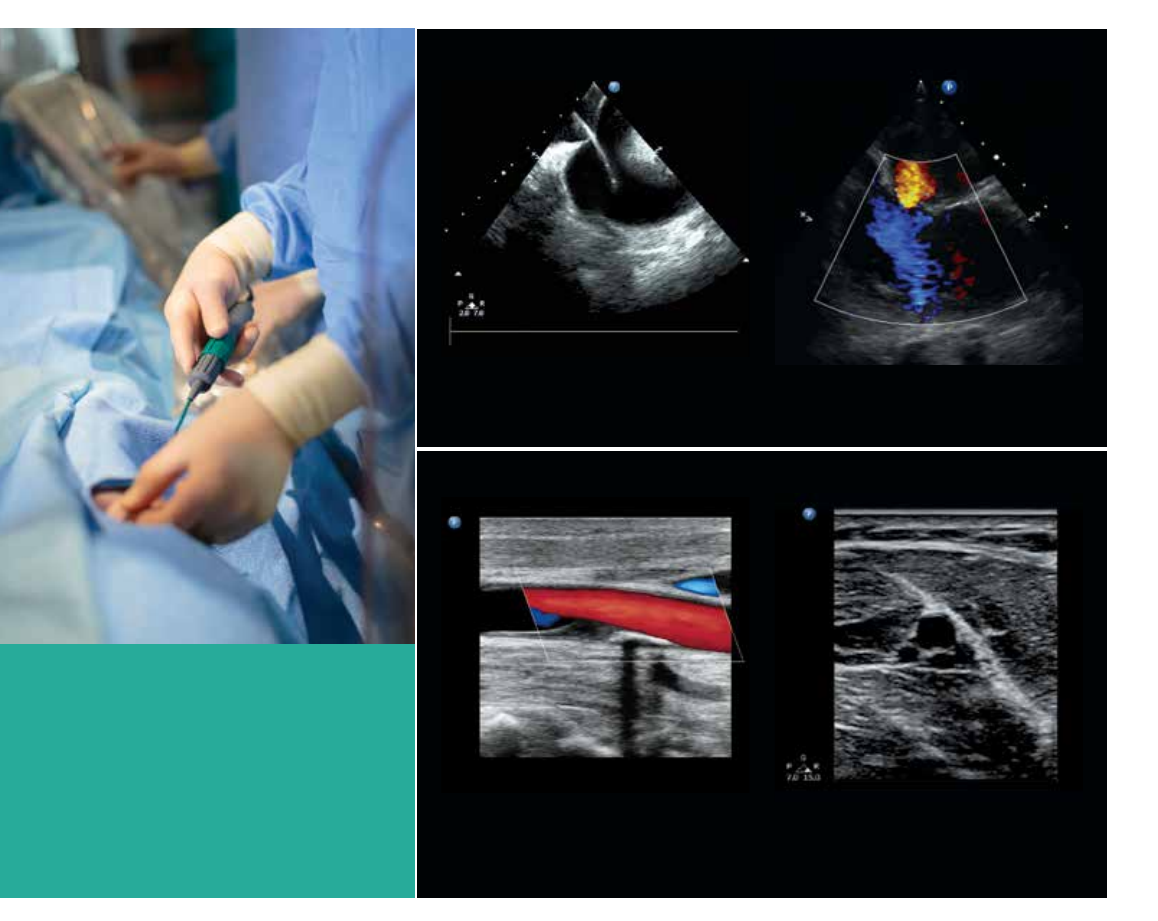

The compact size of CX50 xMATRIX

allows you to have premium

performance for your portable exams.

Easily perform cardiac and vascular

exams at the bedside, and take

advantage of premium image quality

for your critically ill patients.

The fine resolution and highly sensitive color flow

of the L15-7io compact linear array capture this

abnormal vasculature.

Transthoracic imaging using the S5-1 demonstrates

excellent visualization of the entire heart.